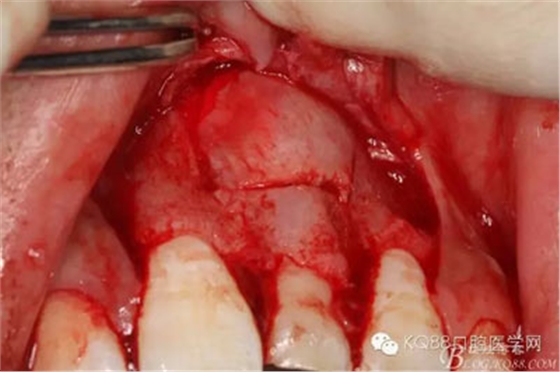

圖8.翻開牙齦粘膜瓣,可見左乳Ⅰ根方骨面隆起

圖9.超聲骨刀去除隆起的骨壁

圖10.形成梯形骨縫

圖11.掀開骨壁。摘除牙瘤及牙囊組織

圖12.摘除囊壁后,暴露出21的切端

圖13.超聲骨刀清理周圍組織,21有Ⅰ°松動

圖14.牙冠周圍滲血多,無法粘結(jié)托槽。位置也高,隨與家屬溝通,暫時保留乳Ⅰ。待21初步穩(wěn)定,再考慮正畸牽引

圖15.輕輕的把21牙冠牽引至乳Ⅰ根尖方向,并擺正牙冠位置。(拔苗助長)

圖16.牙冠上方覆蓋膠原蛋白膜

圖17.骨壁重新覆蓋回去

圖18.縫合